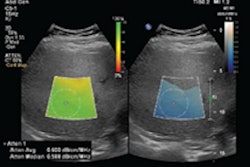

With shear-wave elastography, a newer method for measuring elasticity, an ARFI pulse generates shear waves in a region of interest in a process called point shear-wave elastography (p-SWE) -- or over a larger field of view using 2D or 3D techniques. The speed of the shear wave -- as measured in meters per second (m/s) or kilopascals (kPa) -- indicates stiffness.

Due to artifacts, there is a risk for false negatives with shear-wave ultrasound in the breast, but this can be minimized by using a color-coded "quality map" to evaluate shear-wave propagation and image quality, they advised. Combining strain elastography with shear-wave elastography can also help minimize artifacts that result in false-negative results.

"Therefore, the recommendation is to apply a large amount of gel and then place the [ultrasound] transducer on the breast," Ferraioli et al wrote. "The subcutaneous fatty tissue should appear in dark blue. If it appears in green or even red [that means] too much pre-compression is used and needs to be corrected."